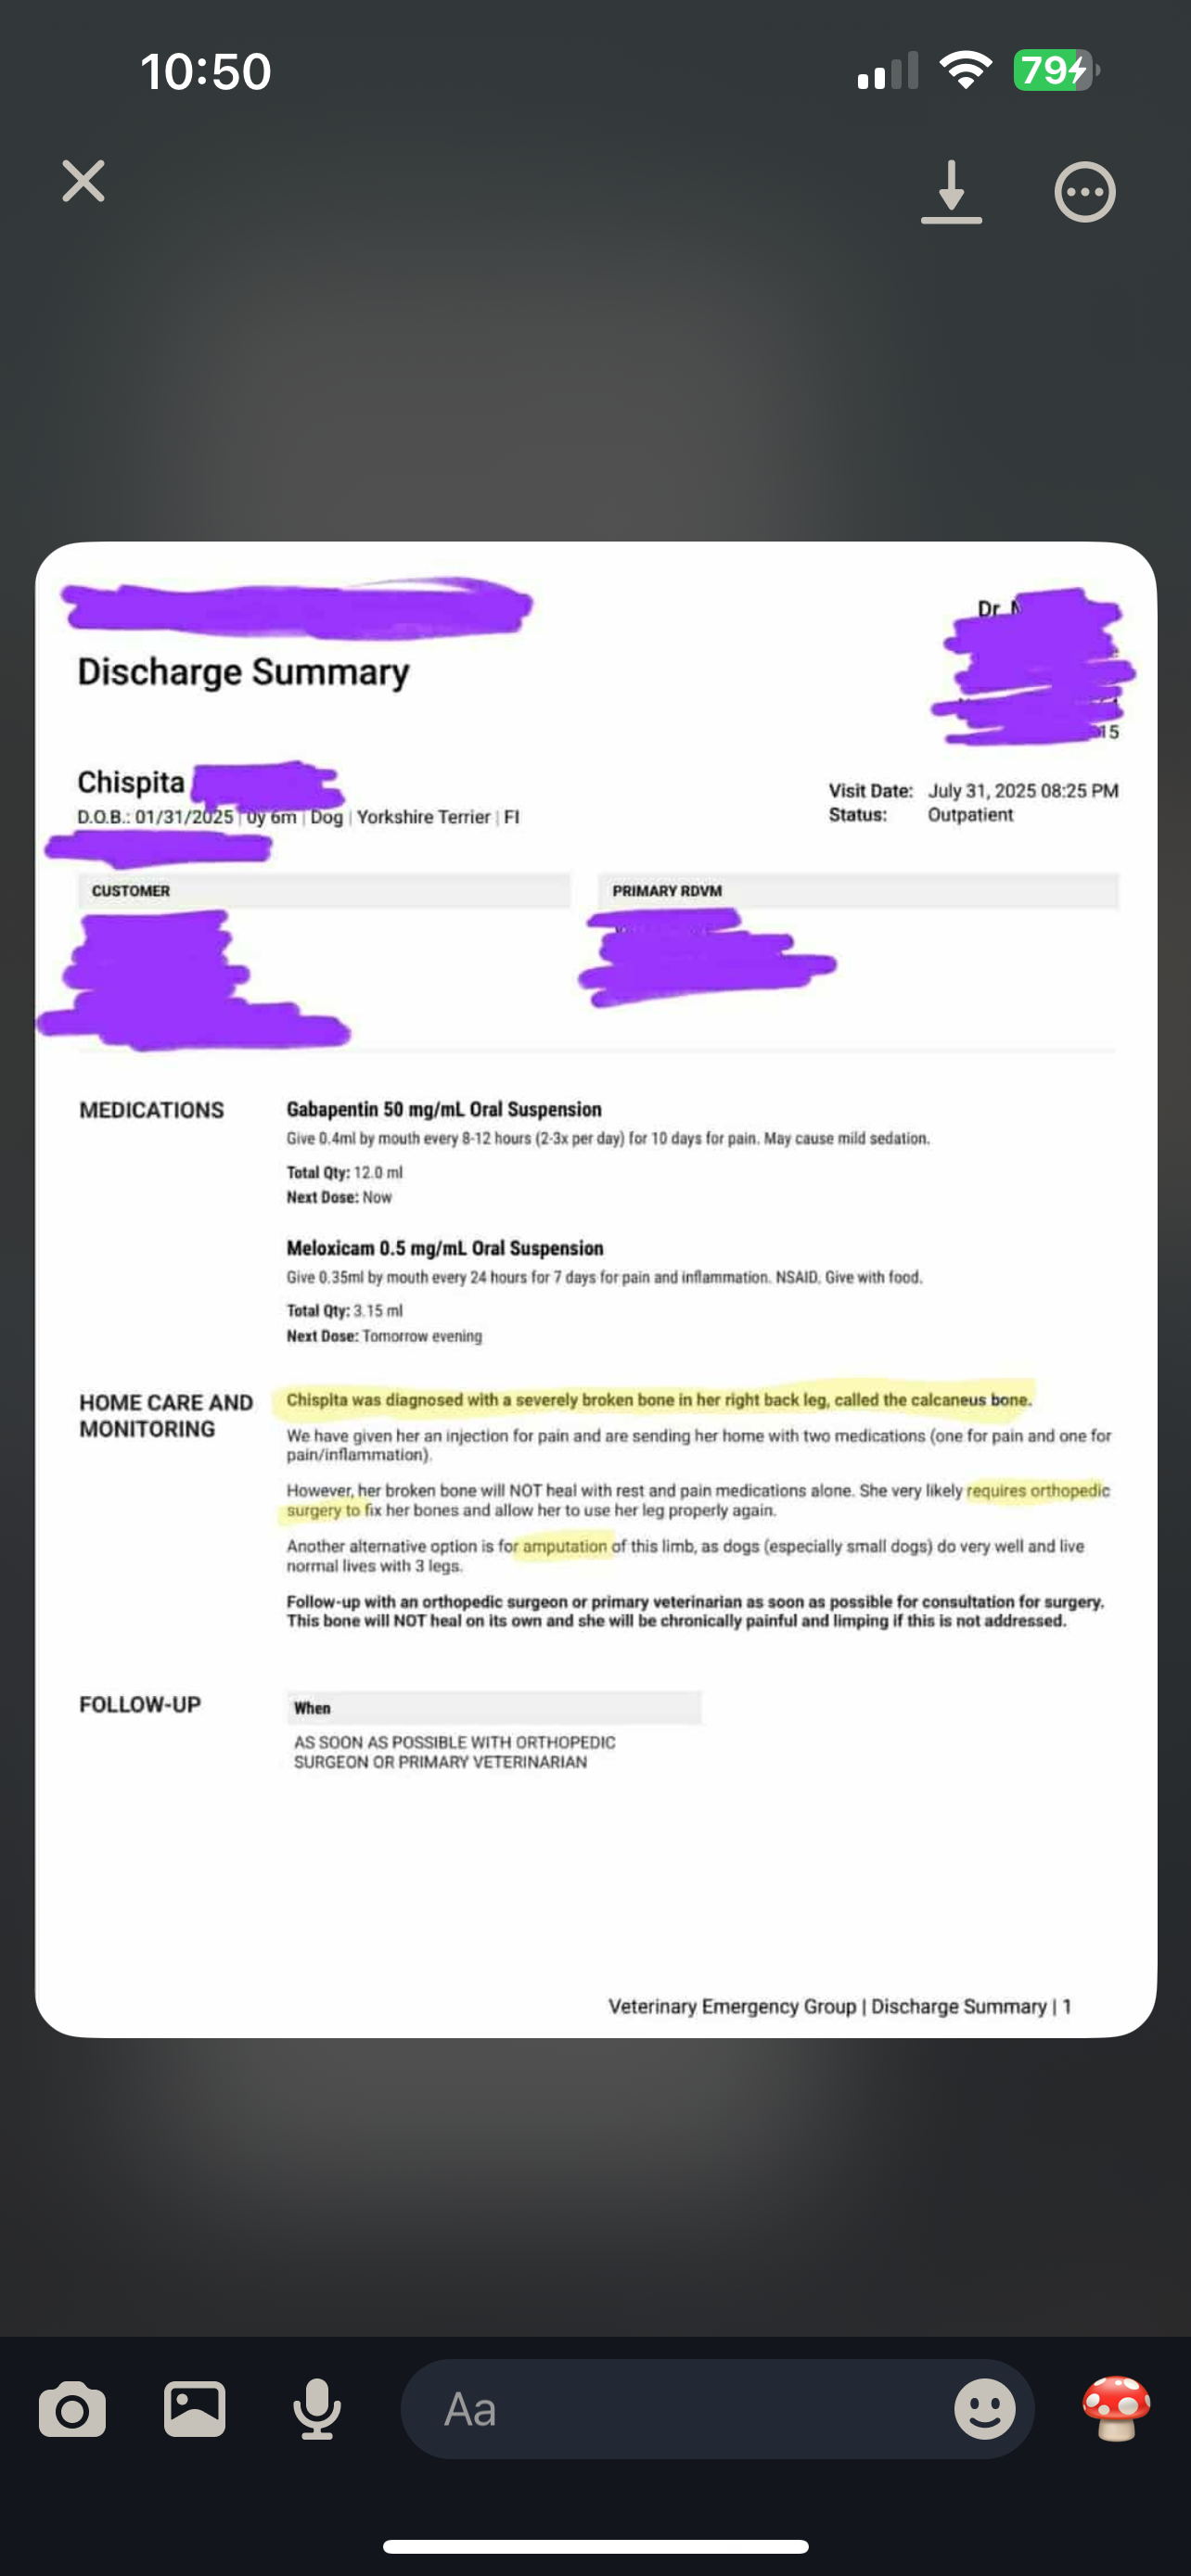

Chispita is my sister’s beloved 6-month-old yorkie mix puppy, and she’s always been a source of joy and comfort for their family. Recently, Chispita suffered a broken heel and now can’t walk or play like she used to. It’s heartbreaking to see her in pain, especially knowing how much she means to my sister and her two young children.

My sister is the only provider for her family. Her partner recently lost his job, and with two kids to care for, covering the cost of Chispita’s urgent surgery is overwhelming. The veterinarians have said that Chispita needs surgery as soon as possible to repair her heel. Without it, she may lose her leg. My sister has already spent a lot on initial exams and treatment, but the surgery and follow-up care are more than she can manage alone right now.

I’m organizing this fundraiser to help my sister give Chispita the care she needs. Every donation will go directly toward the surgery, post-operative care, and any additional treatments to help Chispita recover and return to her happy, playful self. Your support will make a real difference for this family during a very difficult time.

Chispita es la perrita mestiza de yorkie de 6 meses de mi hermana, y siempre ha sido una fuente de alegría y consuelo para su familia. Recientemente, Chispita sufrió una fractura en el talón y ahora no puede caminar ni jugar como antes. Es desgarrador verla con dolor, especialmente sabiendo cuánto significa para mi hermana y sus dos hijos pequeños.

Mi hermana es la única proveedora de su familia. Su pareja perdió recientemente su trabajo y, con dos niños a su cargo, cubrir el costo de la cirugía urgente de Chispita es abrumador. Los veterinarios han dicho que Chispita necesita la cirugía lo antes posible para reparar su talón. Sin ella, podría perder la pierna. Mi hermana ya ha gastado mucho en exámenes y tratamientos iniciales, pero la cirugía y el cuidado posterior son más de lo que puede manejar sola en este momento.

Estoy organizando esta recaudación para ayudar a mi hermana a darle a Chispita la atención que necesita. Cada donación irá directamente a la cirugía, el cuidado postoperatorio y cualquier tratamiento adicional para ayudar a Chispita a recuperarse y volver a ser la perrita feliz y juguetona que es. Su apoyo marcará una verdadera diferencia para esta familia en un momento muy difícil.